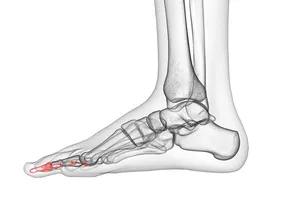

9. 골절

외부의 강한 충격이나 외상으로 인해 뼈가 부러지는 것을 말합니다. 골절 부위는 심한 통증과 부종을 동반하며, 경우에 따라 변형이나 기능 장애가 발생할 수 있습니다. 골절의 정도와 위치에 따라 깁스 고정, 수술 등 다양한 치료 방법이 사용됩니다.